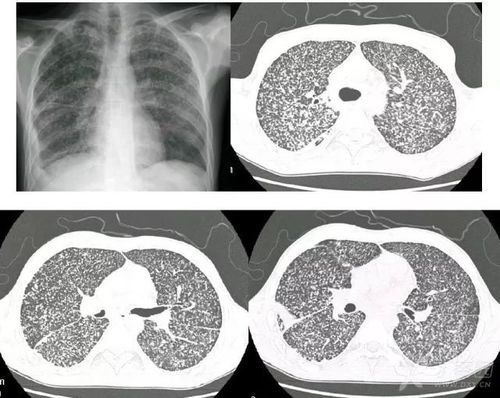

左肺上叶错构瘤